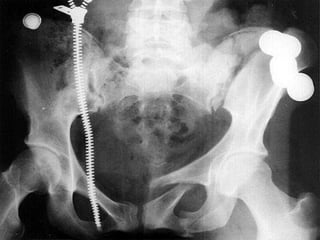

Tile C1/ Young VS